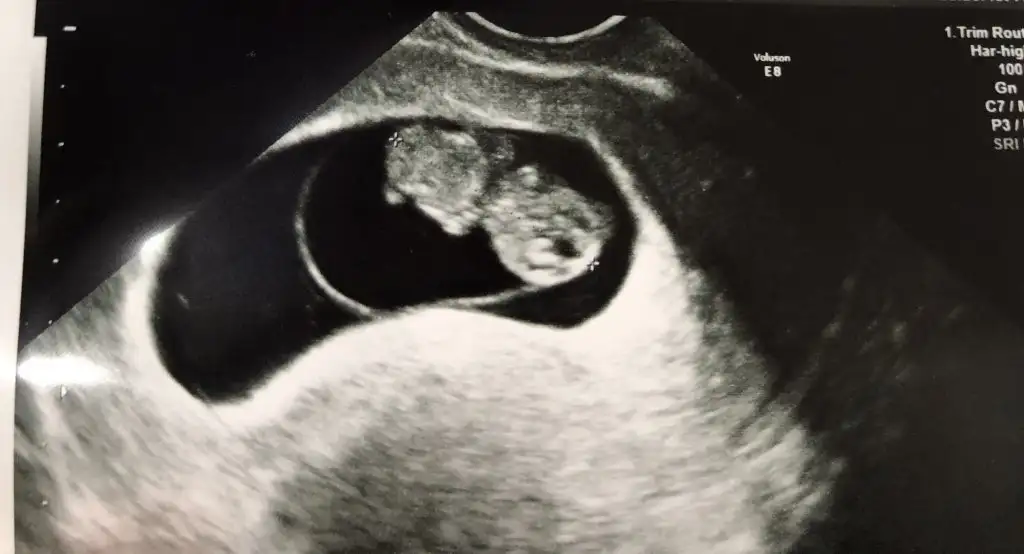

Bebek solda gözüküyor erkek galiba

Asistan, yanlış yönlendirmeyelim lütfen.

Bu bebek kocaman olmuş, maşallah.

Hareketlere de başladığına göre 9+4 falan mı?